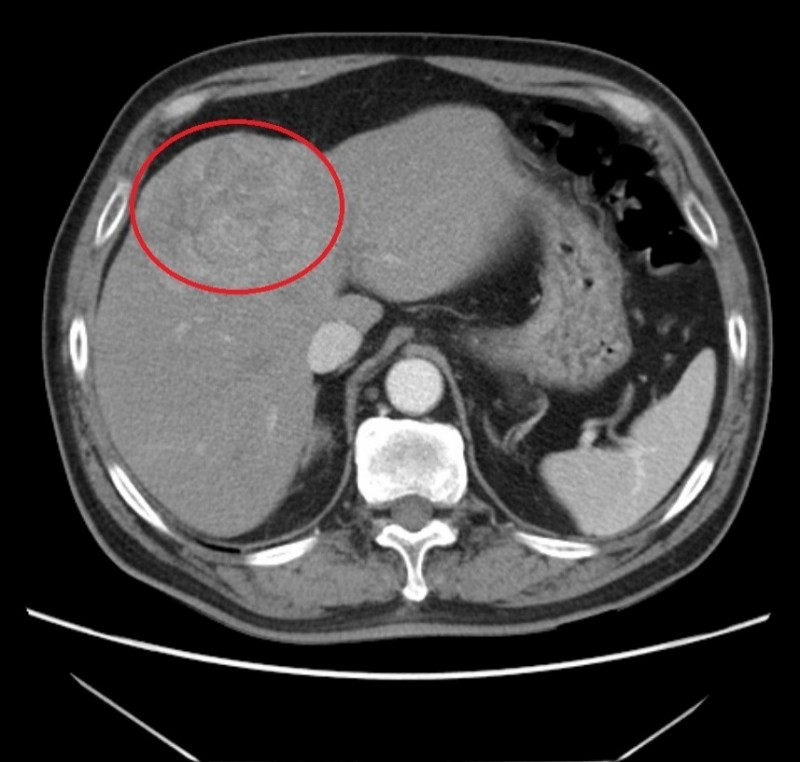

苗栗縣60歲王姓男子,不菸不酒,體檢時發現「胎兒蛋白」的數值高於標準值,進一步檢查,竟發現肝臟有一顆大於7公分的腫瘤;他經醫師調查疾病史,才明白自己是B型肝炎帶原者。王男在醫師建議下,接受第1次肝臟局部栓塞治療,並搭配B型肝炎治療,腫瘤縮小、胎兒蛋白指數也明顯下降,目前控制穩定,於門診定期追蹤治療。

Q:我今年48歲,高中時曾因急性B型肝炎住院,當時皮膚、眼睛都變黃了,出院後,追蹤了一段時間。醫師說我的B肝好了,肝指數也都很正常,我就沒有繼續看診。最近因為腸胃不適就醫,超音波檢查竟然發現肝臟有一顆腫瘤,又做了電腦斷層,診斷為肝臟增生性結節,目前確定我沒有B型肝炎或C型肝炎帶原,但為什麼還會還長出